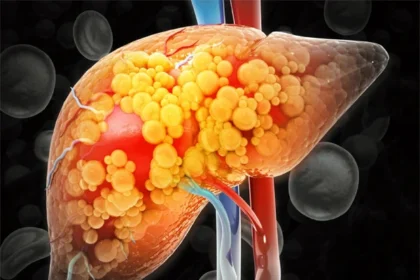

Artificial Sweetener May Cause Liver Disease, Study Finds

A new study has found that sorbitol, which is widely used as a low calorie…